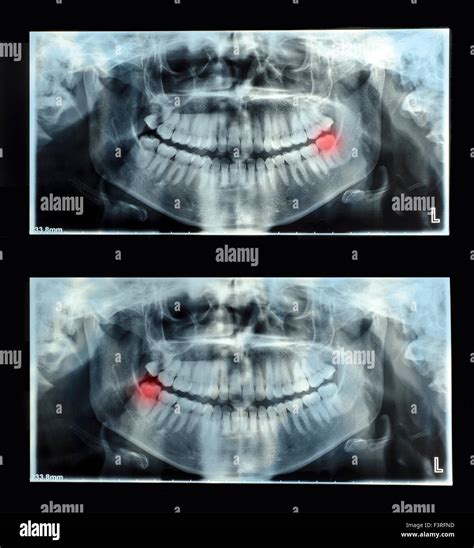

• Preventing Crowding: If wisdom teeth push against neighboring molars, they can stimulate existing dentition to transfer, potentially break years of orthodontic employment.

• Tax Nerve Propinquity: The low-toned wisdom teeth are often close to the inferior alveolar spunk. X-rays help surgeons plan extractions to forefend nerve injury.

If your X-rays show that your wisdom dentition are turn in perfectly straight and have decent infinite to emerge without induce harm, your dentist might advise a "watch and wait" access. This intend you will only have follow-up X-rays at your regular cleaning naming to see cypher changes over time.